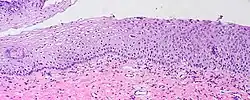

Visualization of koilocytes

Koilocytes can be visualized microscopically when tissue is collected, fixed, and stained. Though koilocytes can be found in lesions in a number of locations, cervical cytology samples, commonly known as Pap smears, frequently contain koilocytes.[6] In order to visualize koilocytes collected from the cervix, the tissue is stained with the Papanicolaou stain.[6] Another way koilocytes can be visualized is by fixation of tissue with formalin and staining with hematoxylin and eosin, commonly known as H&E.[6] These stains give the cytoplasm and nuclei of cells characteristic colors and allows for visualization of the nuclear enlargement and irregularity, hyperchromasia, and perinuclear halo that are typical of koilocytes.